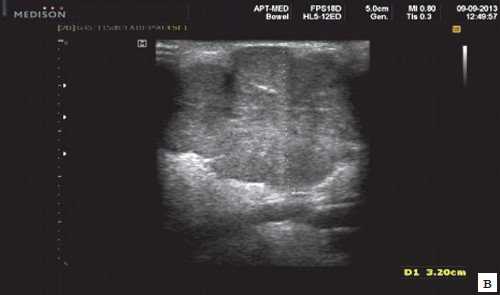

Рис. 3. Сиаладенит правой поднижнечелюстной слюнной железы.

Рис. 5. Камень протока поднижнечелюстной слюнной железы.

Рис. 6. Камень в паренхиме поднижнечелюстной слюнной железы.

Рис. 7. Камень в протоке поднижнечелюстной слюнной железы.